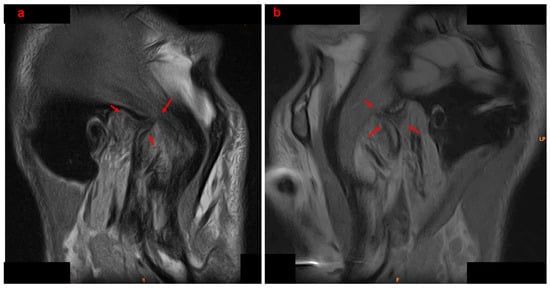

An Innovative Approach to Managing Temporomandibular Disorders Through the Combined Use of Two Oral Devices: A Case Report

by Antonio Spagnuolo, Roberta Iacono, Gian Mauro Liberatore and Carlo Di Paolo

Appl. Sci. 2026, 16(1), 273; https://doi.org/10.3390/app16010273 - 26 Dec 2025

Temporomandibular disorders (TMD) are increasingly prevalent in the adult population. Given the multifactorial and often chronic nature of TMD, the ideal therapeutic approach must be multimodal and personalized, with a preference for conservative treatments. However, standardized protocols combining occlusal devices and biobehavioral therapy for internal derangement (ID) are still lacking. Case Presentation: A 20-year-old male patient presented with bilateral anteromedial reducible disc displacement, with intermittent locking on the right. He reported joint noises, difficulty chewing, and occasional painful mouth opening. A comprehensive diagnostic workup, including clinical, functional, and radiographic evaluations, was performed. The patient underwent a biobehavioral gnathological therapy involving two oral devices: RA.DI.CA. and By-Te ® Reali. The protocol included personalized exercises, patient education, and behavioural counselling. Results. The patient achieved full remission of pain, disappearance of joint noises, and restoration of mandibular function, without dental movement. Pre- and post-treatment MRI and condylography confirmed improved condyle-disc relationships, increased intra-articular space, and better symmetry of movements, particularly on the right. Conclusion. The combined use of RA.DI.CA. and by-Te ® Reali devices, supported by a personalized functional programme, appears effective in managing TMD with ID. Further studies on larger populations are needed to confirm the efficacy and safety of this protocol. Full article